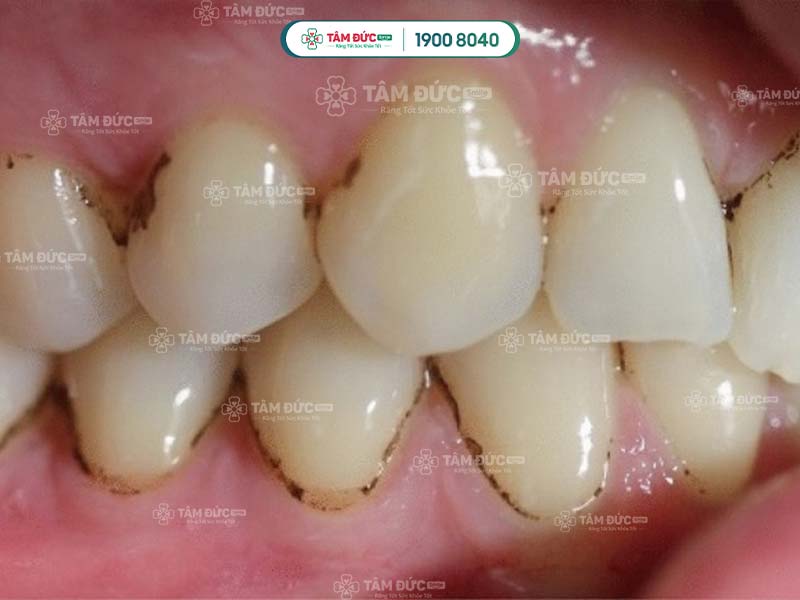

cao răng đen quanh chân răng

Cao răng bị đen là dấu hiệu cảnh báo sâu răng đang tiến triển

3.1. Gây viêm nướu, viêm nha chu

Cao răng bị đen rất dày và cứng, là nguyên nhân chủ yếu làm nướu bị viêm hoặc nhiễm trùng. Có rất nhiều vi khuẩn trú ngụ trong cao răng đen, dần phá hủy men răng, làm tình trạng viêm nướu ngày càng nghiêm trọng. Nguy hiểm nhất chính là làm hư tổn tổ chức nha chu.